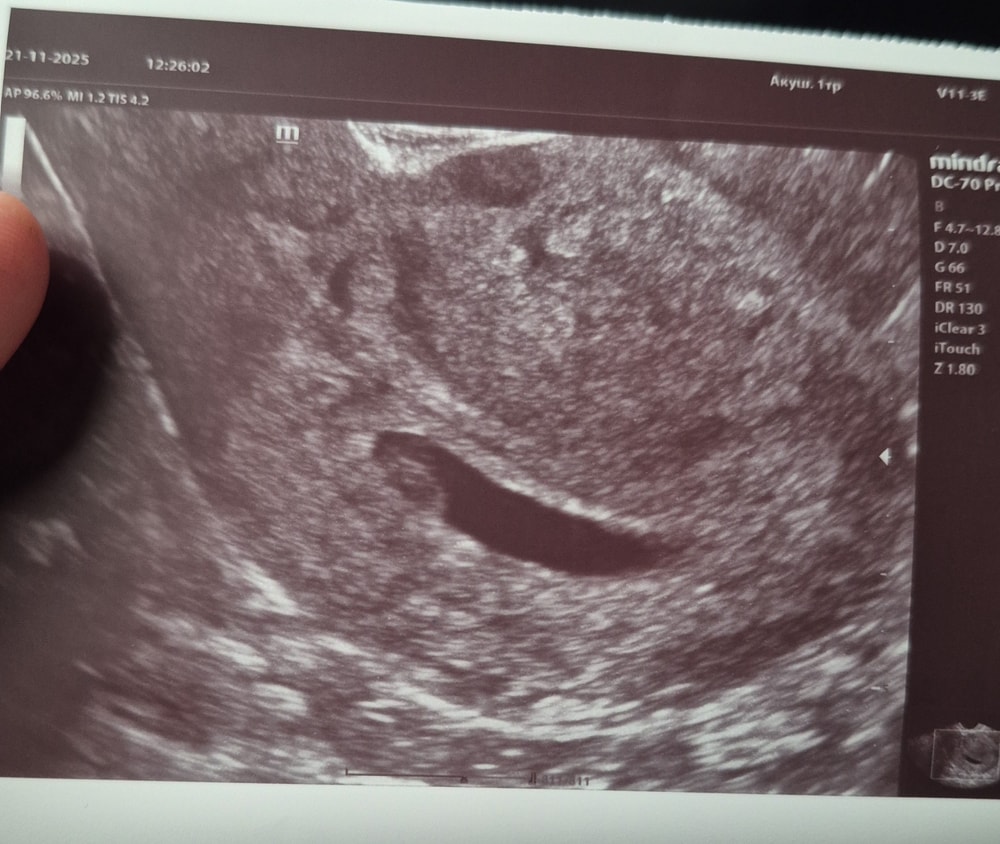

Второе узи

У нас получилось! Я беременна!И так , первое узи было 8 ноября, где подтвердили маточную беременность. Второе узи вчера, 21 ноября. Сердечко бьётся🙏ктр 7.8 мм, желточный мешок 3.4 мм. По узи срок 6.5 недель. Фото получилось не очень , эмбрион спрятался где - то в углу. Но это и не главное. Главное, все хорошо. Из симптомов чувствительная грудь и отсутствие аппетита ((( . Но так было и в первую беременность.